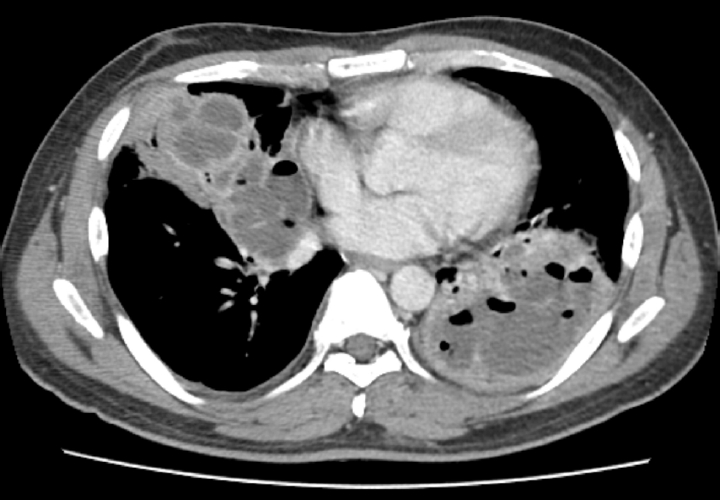

- Case ReportMar 11, 2026 Severe bilateral hydrocarbon pneumonitis requiring surgical drainage following accidental aspiration of industrial cleaning solvent in a seafarer: a case report Sang-Heon Cho, Jong Gill Jeong Ann Occup Environ Med 2026;38:e8.

Severe bilateral hydrocarbon pneumonitis requiring surgical drainage following accidental aspiration of industrial cleaning solvent in a seafarer: a case report

Sang-Heon Cho, Jong Gill Jeong

Ann Occup Environ Med 2026;38:e8.